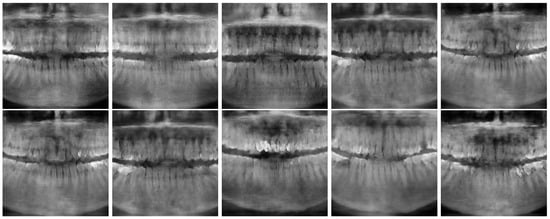

Figure 6 and Figure 7 show the best and worst generated images, respectively, as determined by the average scores for all twelve criteria. The best images show a reasonable depiction of both the overall morphology and certain details, although not at the level of contemporary real-world panoramic radiographs. The worst images display various issues, including poor overall image quality and manifestations of extra rows of tooth crowns.

Figure 6. Best images generated using Models 1 (top row) and 2 (bottom row).